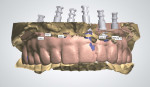

In the dental laboratory, scan bodies were placed on the abutment analogs. These are the equivalent of digital impression copings. The cast with scan bodies was scanned in a desktop lab scanner (Figure 8). Once scanned, the scan bodies were aligned using a library of supported implant interfaces. This allows the design software to create a precise fit of the prosthesis to the abutment.

The cast of the immediate-load hybrid prosthesis was scanned (Figure 9). The opposing cast was scanned, and the three scanned casts were merged (Figure 10). Using the superimposed scan of the immediate-load prosthesis as a guide, library teeth from the database in the CAD system were selected and placed in their appropriate locations. Connectors, screw-access holes, and gingival tissues were designed (Figure 11). Once the design was finalized, the design file was sent to the CAM workstation where it was nested in a polymethyl methacrylate (PMMA) block. The CAM software computed the tool path for the milling machine, and a PMMA replica of the final restoration was milled. Metal interfaces were cemented into the PMMA replica and it was returned for try-in (Figure 12).

The most common post-treatment complication of a porcelain-fused-to-zirconia restoration is porcelain chipping.12,13 In this case, all of the occluding surfaces were to be in zirconia, while the labial aspect of the six anterior teeth were to be layered feldspathic porcelain. This would decrease the chance that occlusal forces would cause porcelain chipping. This cut-back was accomplished in the design software, which thus completed the design process. The final digital design was transferred to the CAM workstation where it was nested in a zirconia block (Ceramill® zolid, Amann Girrbach AG, www.amanngirrbach.com) and then milled (Figure 14). The zirconia block was in a pre-sintered or “green” state. Fine detail was then carved into the milled zirconia block using diamond burs, diamond discs, and hand instruments.